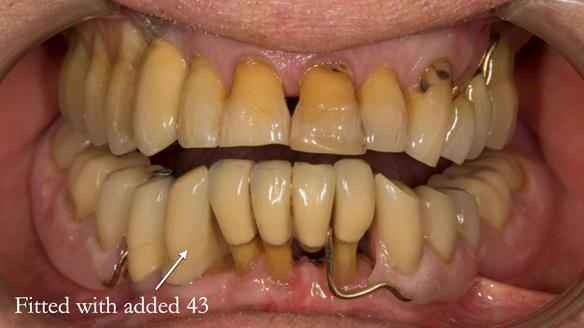

In 2022, tooth 43 fractured.

An artificial tooth was added to the RPD

by welding a cobalt–chrome tag to the bar

and adding the tooth.

The denture continued to function extremely well.

This case was always about function, not aesthetics.

Ken’s teeth were never going to look perfect.

There were stained composites, old restorations, and obvious wear.

That was accepted from the outset.